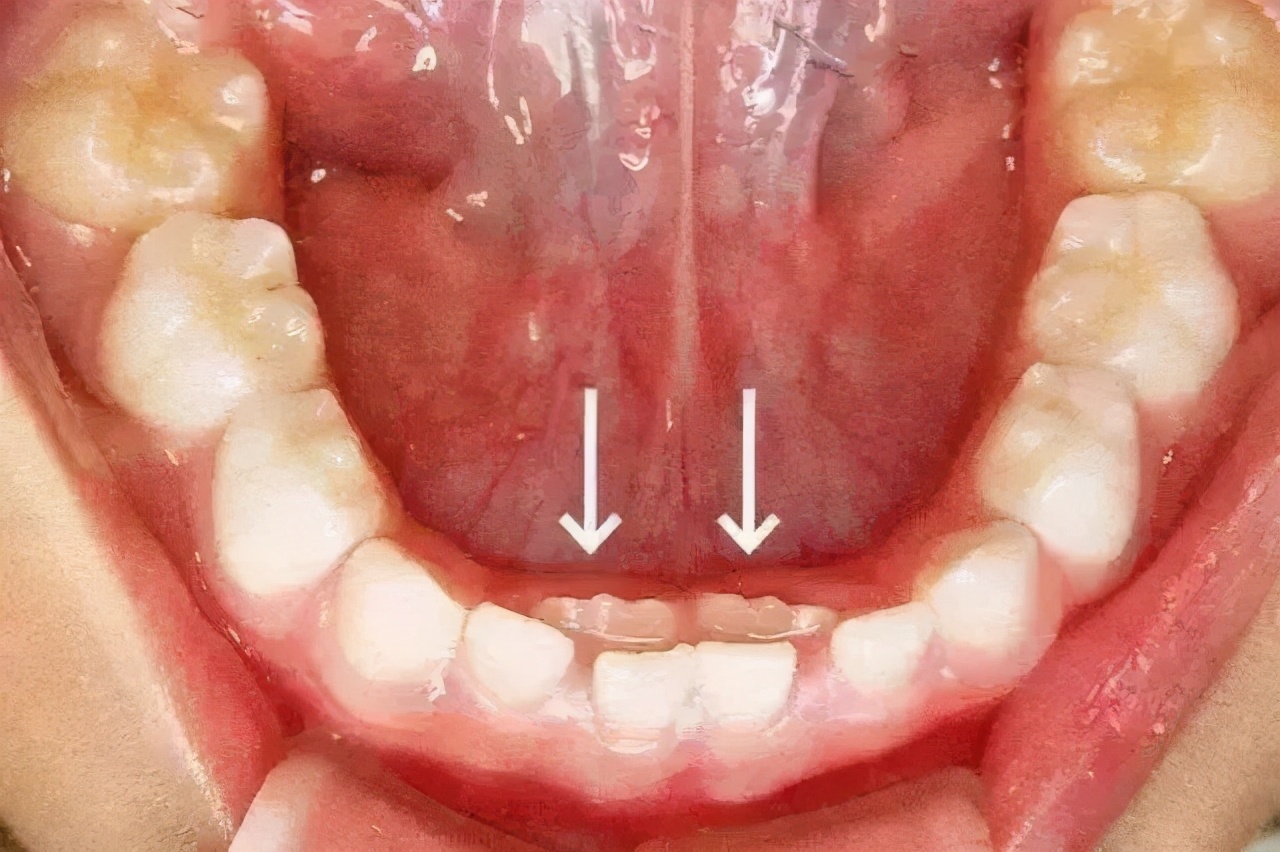

换牙时的注意事项0 1乳牙异常萌出1)保留乳头乳牙脱落有一定的时间和顺序。它应该掉下来而不会掉落。在医学上称为乳牙固位。乳牙的固位通常会导致恒牙无法在正常位置喷发。一些儿童的恒牙已经萌出,但乳牙却经常拒绝“屈服”,迫使恒牙从乳牙内侧长出牙齿,形成“双层牙齿”现象。

在这种情况下,您应该尽快带孩子去医院去除剩余的乳牙,以使恒牙能够正常爆发。保留乳牙的原因很多。最常见的是孩子吃得太细了,没有充分发挥牙齿的生理刺激作用,在大约2岁半左右宝宝的乳牙全部萌出后,应该多吃富含纤维的食物和有一定的硬度。通过咀嚼作用,它们将影响咀嚼肌肉的运动,加速血液循环,并促进牙龈,颌骨和面骨的发育。

3)乳牙难萌出如果乳牙过早脱落,孩子将不得不用口香糖咀嚼,舔舔和吮吸一段时间,这将导致口香糖变厚,使牙齿难以发芽。换牙时,前恒牙从乳牙的下侧或内侧突出。喷出的恒牙与成人的牙齿大小相同。轻微拥挤和扭曲是正常现象。他们将根据相邻牙齿的萌出以及颌骨的生长和发育来调整行数。02纠正孩子的不良习惯在更换期间,乳牙和恒牙共存。恒牙刚刚爆发,特别是“咬牙的关键”“第六年龄的牙齿”。它们尺寸大,在咬合面上有很多凹坑和裂缝,并且倾向于保留食物残留物。大多数儿童没有彻底刷牙,而且经常容易龋齿,因此应该教给儿童正确的刷牙方法。此外,当乳齿松弛并即将脱落时,孩子们经常用舌头舔那些松弛的牙齿。这是个坏习惯。还有一些不良的口腔习惯,例如口呼吸,吮吸手指,咬住被子角,抱着婴儿奶瓶,咬住上下嘴唇,舌头,反吞咽等,也会影响牙齿的发育弓,导致咬合,突出和向上和向下收缩,必须纠正。